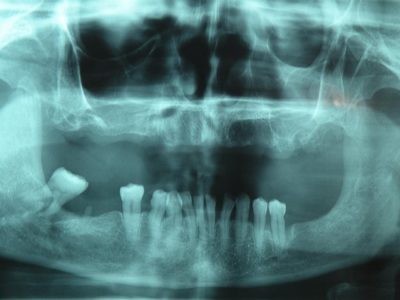

An implant is actually the replacement for a root of a tooth. It is a screw of precisely defined size that is installed in the bone of the jaw. It is made of titanium, a precious metal, the only one compatible with human bones. The decision of the installment of the implant is made on the basis of a digital orthopan and a computed tomography (CT), i.e. the scan of the jaw. One or more teeth can be replaced with the help of implantology, and the implant is the base, or, rather, the carrier of the prosthetic replacement. Prosthesis and dental bridges can be attached to the implants, but one implant can also replace only one tooth if only that one is missing from the teeth row.

Prosthesis on implants are an ideal solution for patients who have a strong and healthy jaw but complete loss of teeth. They can be installed on the upper or lower jaw and they are extremely easy to maintain hygienically. There are two types of prosthesis on implants: ones are impacted (supported) with crossbars, and the others are supported with spheres (trackers). After a detailed analysis of the overall situation in each patient, a stomatologist has to define the type of retention adequate for each individual patient.

Dental bridges on implants are used to lower the loading from the individual implant, i.e. in the cases when the patient misses more than one tooth. The process of installation of dental bridges on the implants differs from the one of the prosthesis installation. Namely, the implantation and the time necessary for the doctor to assure that the implants are completely integrated in the bones, follows the implant impression making and the installation of the upgrades (which „imitate“ the tooth). Dental bridges are installed on those upgrades.